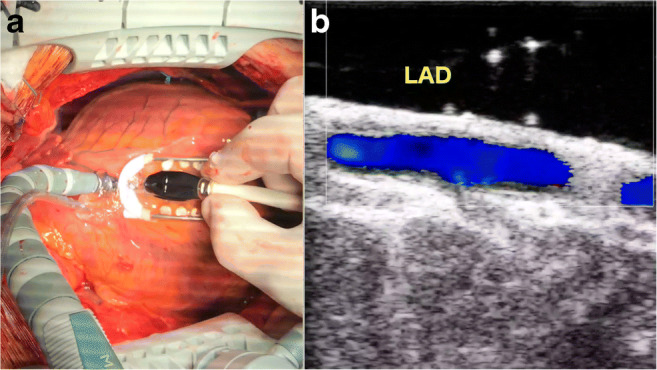

We routinely use imaging in off-pump CABG to measure the lumen of the vessel at the level of the anastomotic site after stabilization to choose the dimension of the shunt that should be used (Fig. 1).

Fig. 1.

a HR-ECUS probe on the LAD. b Imaging of the anastomotic site on the LAD

The left main can be scanned in longitudinal and cross section views. Scrolling the probe distally in short axis view at the level of the bifurcation, the LAD will be on the right and the LCx on the left. If there is a ramus intermedius, it will appear between the LAD and LCx (Fig. 2).

Fig. 2.

Trifurcation of the left main stem. Short axis view